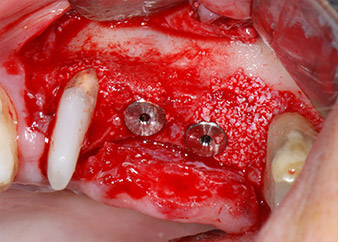

The implants (Restore, Keystone Dental, diameter 3,75 mm, length 8.0 mm) were placed with the implant motor

(Figs. 11 and 12).

Bone deficiencies around the implants, at the mesial aspect of tooth 27 and around the buccal root of tooth 24, were filled with xenogeneic bone substitute particles and covered with an absorbable collagen membrane (Bio-Gide, Geistlich Biomaterials) for GBR augmentation (Figs. 13 and 14).